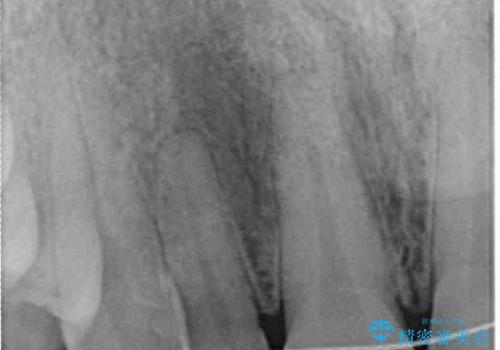

- ラミネートベニアと歯の境目の着色を気にして来院された患者様です。

矯正治療後に矮小歯であった歯をラミネートベニアにて形を変えたそうですが、矯正歯科治療直後であったためか、歯肉の位置が変わったことで境目が見えていました。

着色の原因として、湿気の多い環境で接着操作を行うと、境目に細かいギャップができてしまうことが考えられます。

接着の際にはラバーダムを使用して、乾燥した環境を整えて処置を行いました。